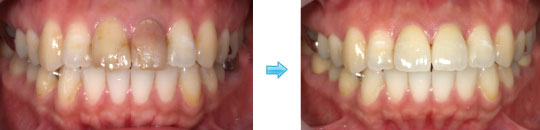

オールセラミック クラウン 症例

最少の骨外科処置を行い、歯槽骨と歯肉の調和を図ることにより、予知性が高まります。